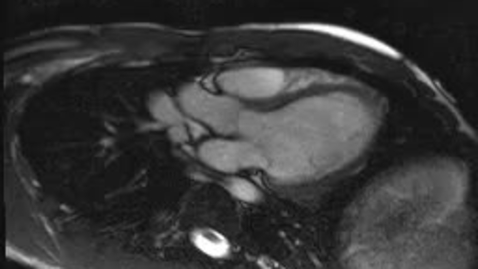

Hypertrophic cardiomyopathy

Panel B Clip: Hypertrophic cardiomyopathy

Panel A Clip: Normal